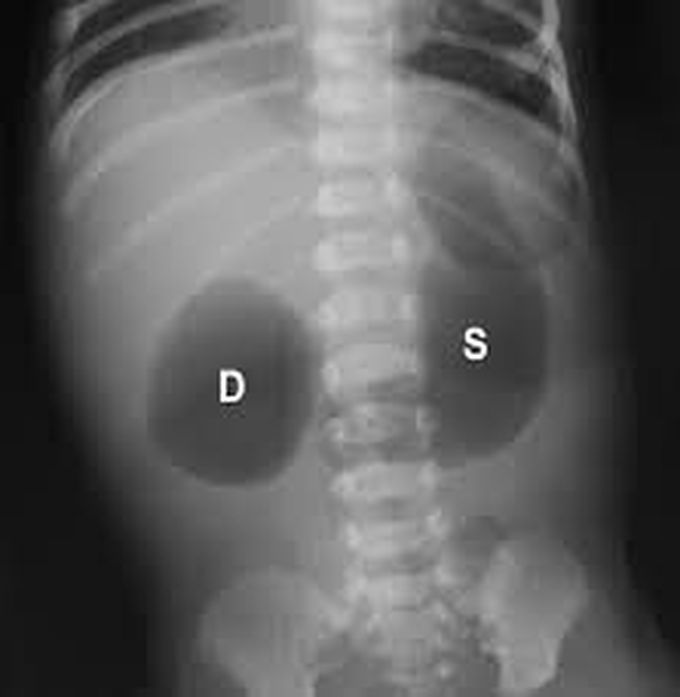

Double Bubble sign is a classical radiological sign commonly seen in duodenal atresia. It is often observed in infants as dilatation of proximal duodenum and stomach, giving an appearance of two bubbles ( hence double Bubble). Other uncommon causes may include: Duodenal stenosis Midgut volvulus Superior mesenteric artery syndrome Annular pancreas Choledochal cyst Ref: Reeder Maurice Merrick and Benjamin Felson. Reeder and Felson's gamuts in radiology. Springer, 2003. ISBN: 0387955887, 9780387955889.